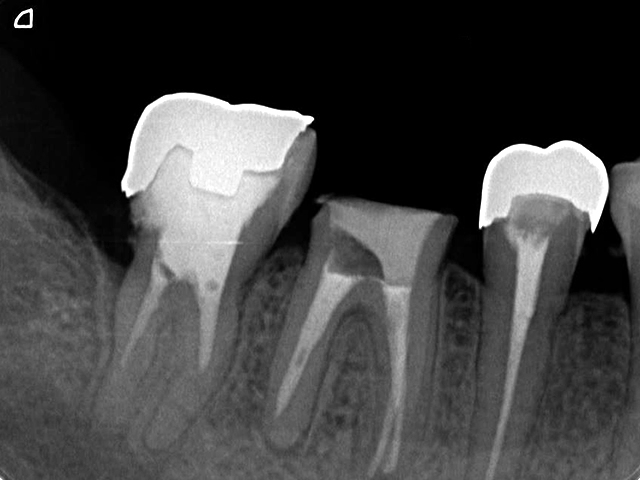

< 症例1 >

- 歯周再生療法

歯周病で破壊、吸収された歯周組織は、その原因を除去することで再生しようとしますが、歯周病に罹患した部分を清掃した後に何もせずそのまま治癒を待つと必要な支持組織が再生する前に歯肉がそこに入り込み歯周組織の再生を阻んでしまいます。GTR法では、歯周ポケット内部を清掃した後にメンブレンと呼ばれる膜を設置し、外から歯肉が入り込まないよう防御することで、メンブレンの下には歯周組織が再生を開始し、ゆっくりと成長していきます。この成長には時間を要しますので、メンブレンの下が新しい組織で満たされるまで一定期間保持しておく必要があります。

GTR法は、歯肉が入り込むのを膜を用いて阻止しますが、エムドゲイン法では、エムドゲイン・ゲルという薬剤を欠損部に注入し、歯周組織の再生を促すとともに、歯肉が入り込むことを防止します。このエムドゲイン・ゲルは時間の経過とともに歯周組織の再生を促しながら吸収していくので、GTR法のように後からもう一度手術を行う必要はありません。